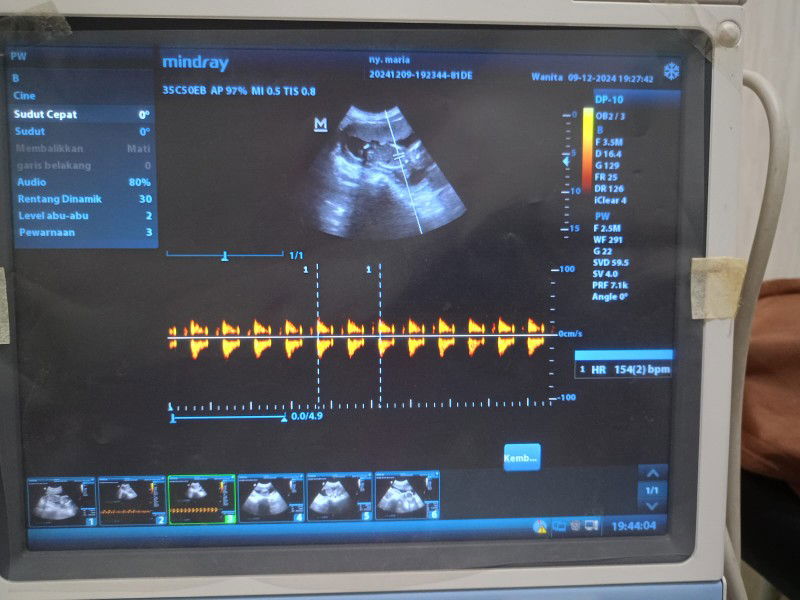

Bantu jawab ya sama sarannya bund saya kehamilan pertama atau baru